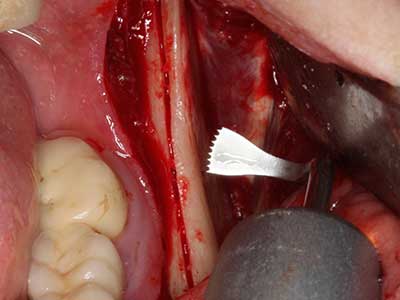

La piezochirurgia presenta altri vantaggi per quanto riguarda la raccolta di blocchi ossei. Oltre all'elevata precisione dell'osteotomia appena descritta, l'utilizzo di puntine per sega molto sottili permette di minimizzare in maniera significativa la perdita di materiale. È molto probabile che si verifichi una maggiore perdita di materiale durante la raccolta utilizzando puntine di strumenti più spessi, in particolare delle frese Lindemann (Lakshmiganthan, Gokulanathan et al. 2012). La separazione basale, necessaria in particolare per i trapianti di blocchi nella zona retromolare, viene semplificata grazie a seghe specificatamente progettate di forma rettangolare; di conseguenza la piezochirurgia è considerata una procedura precisa, semplice e sicura per la raccolta di blocchi di osso nella zona retromolare (Happe 2007) (figg. 1-12).